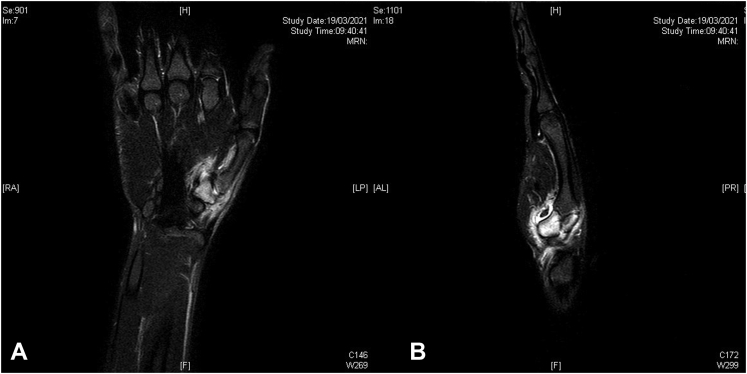

Figure 2.

A Sagittal and B longitudinal views of the MRI examination performed before surgery. The bone aspect is better represented in the CT examination; in fact, the nidus, sclerotic area, and erosion are not visible. The bone edema and flogistic perilesional tissues are visible on the MRI scan.